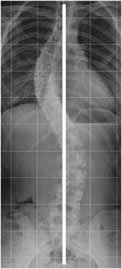

Desbalance coronal:

Se determina con la línea sacra vertical, en la Rx AP. Se traza por la mitad del cuerpo de C7 y normalmente cruza la mitad del sacro. (1, 25, 26). (Fig 32).

Se considera que una escoliosis está compensada, si la distancia en relación con el eje del sacro, es menor de 2 cm. Se habla de balance positivo cuando la distancia es mayor de 2 cm hacia la derecha y balance negativo, cuando la línea se localiza sobre el lado izquierdo. (25, 26). (Fig 33 y 34).

Fig 32. Balance coronal normal.

Rx AP. Línea sacra vertical normal, que pasa por la mitad del cuerpo de C7 y el sacro.